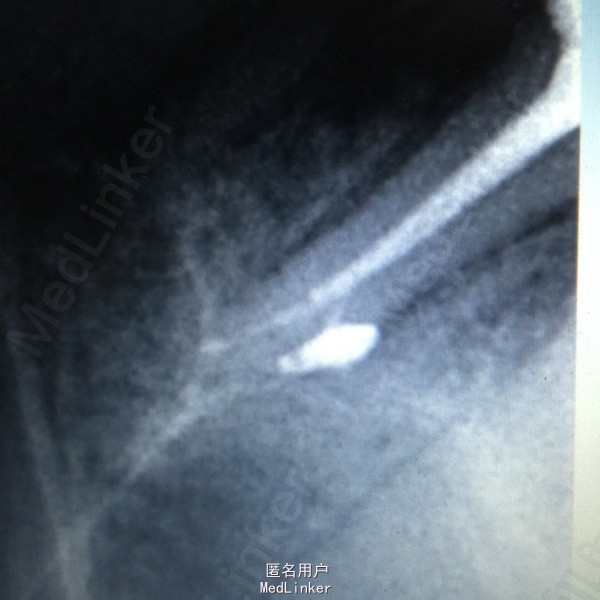

诊断:15慢性牙髓炎急性发作 治疗:一诊:15局麻下开髓揭顶全,去龋净,拔髓,疏通根管,冲洗根管,干燥,FC棉,暂封,告医嘱。 二诊:15去暂封及FC棉,根管长度测量,WAVE-ONE根管预备,冲洗,干燥,根管消毒,Vitapex及大锥度牙胶尖充填,X线示适充, 锌基,树脂充填,调合,抛光,告医嘱。

讨论:牙髓炎及根尖周炎急性期以降低压力为主,随后可进行常规根管治疗。 根充后拍片发现有糊剂从侧支根管溢出,与大家一起分享。